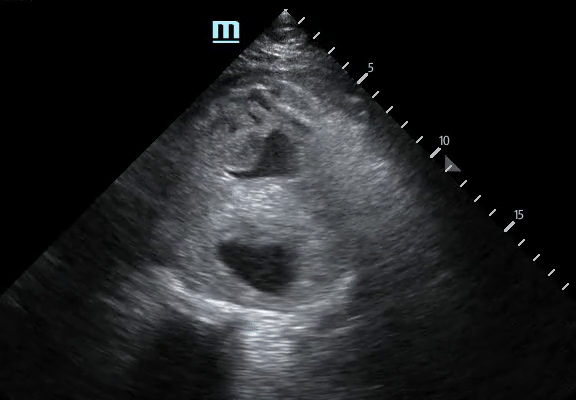

A 61-year-old male was brought in via EMS after a syncopal episode. He was diaphoretic and hypotensive, complaining of severe right flank pain. While IV access was being obtained a bedside ultrasound was performed demonstrating a large abdominal aortic aneurysm with significant heterogeneous intraluminal clot. There is also appreciable focal hypoechoic disruption of the wall of the aneurysm consistent with rupture. The patient was resuscitated in the ED and taken emergently to the OR to surgical repair. Michael Macias, MD @emedcurious